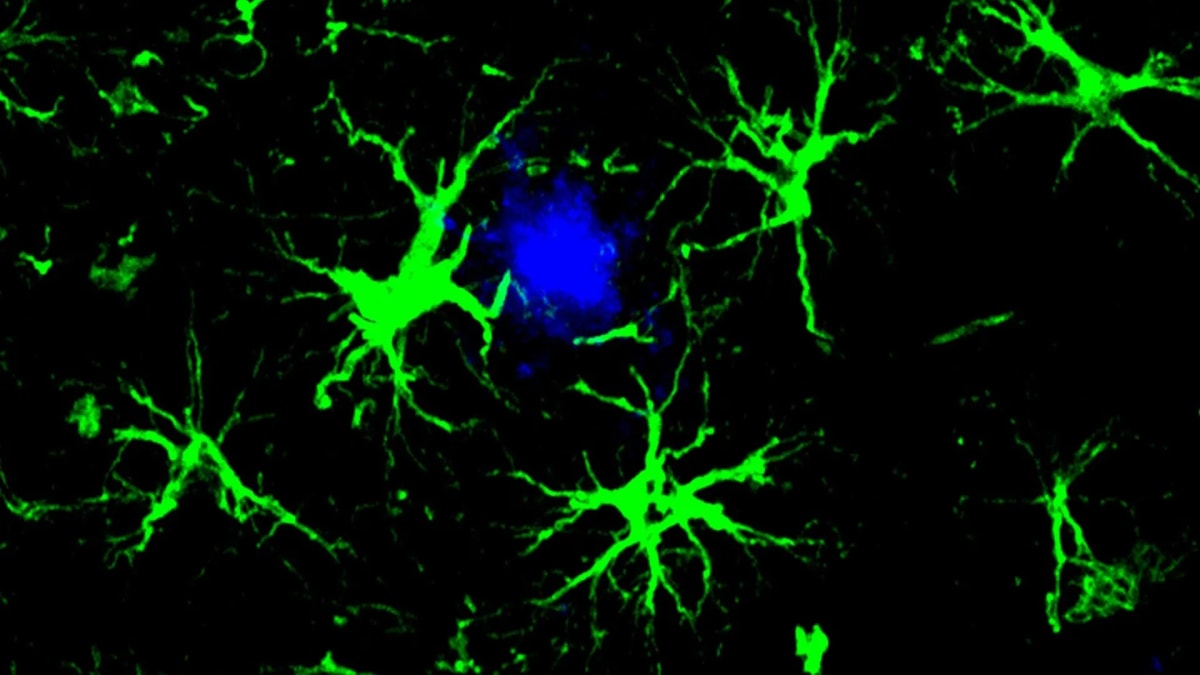

Researchers at the University of California San Diego studied 2,766 women over 25 years, tracking a blood-based protein called phosphorylated tau 217 (p-tau217). This protein is linked to the brain changes that occur in Alzheimer's disease, the most common form of dementia.